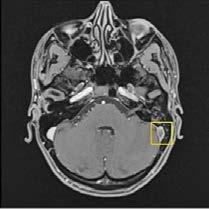

El día 18/2/2022 el paciente refiere dolor torácico. Se realiza un electrocardiograma, que muestra elevación del segmento ST en las derivaciones anteriores en relación con un infarto agudo de miocardio (IAM) anterior. Se activa código infarto y se realiza una coronariografía emergente, que muestra una oclusión de perfil embólico en la arteria descendente anterior media (Figura 1, flecha amarilla). Se trata con trombectomía aspirativa con buen resultado angiográfico final con flujo TIMI 3. Se inicia tratamiento con perfusión de heparina sódica. El día 19/2 el paciente comienza con cefalea muy intensa y afasia, por lo que se activa nuevamente código ictus y se realiza un angioTAC craneal que muestra una hemorragia subaracnoidea (HSA) de predominio izquierdo secundaria a sangrado por un aneurisma disecante de la rama M2 de la arteria cerebral media izquierda (Figura 2, flecha amarilla). Se decide completar estudio con una angiografía que confirma los hallazgos del TAC. Por el alto riesgo de resangrado y la necesidad de anticoagulación oral permanente, se decide embolización del aneurisma con coils, que resulta exitoso (Figura 3, flecha amarilla). Se reinicia durante el ingreso perfusión de heparina sódica y unos días antes del alta se comienza con anticoagulación oral con apixaban 5 mg/12 horas. La evolución clínica es favorable, siendo la exploración física al alta normal. Tras tres años de seguimiento bajo tratamiento con apixaban 5 mg/12 horas no han sido reportados nuevos episodios de sangrado ni de trombosis.

Se realizó una tomografía computarizada (TC) con contraste de forma emergente, que mostró una disección aórtica iatrogénica tipo A focal de origen en la zona 0 del cayado con extensión al tronco braquiocefálico derecho (1) sin afectar al resto de troncos supra-aórticos, cayado o aorta descendente (Figuras 1 y 2); además del hematoma

Figuras 1 y 2: Prótesis aórtica migrada y disección aórtica focal tipo A, de origen en la curvatura menor del arco aórtico (zona 0) hasta la bifurcación de la arteria braquiocefálica derecha; sin afectación de del resto de troncos supra-aórticos, del resto del cayado aórtico o de la aorta descendente.